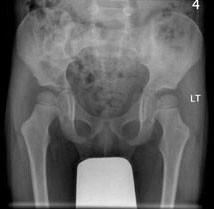

男,请根据其正常骨盆影像图像,判断其最可能的年龄 ( )A、10岁左右B、13岁左右C、4岁左右D、7岁左右E、1岁左右

问题 男,请根据其正常骨盆影像图像,判断其最可能的年龄 ( )

选项 A、10岁左右 B、13岁左右 C、4岁左右 D、7岁左右 E、1岁左右

答案 C